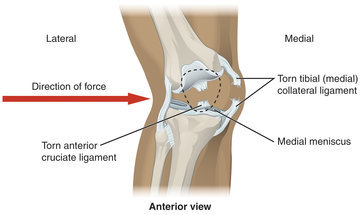

Немецкие специалисты нашли способ лечения остеоартрита колена, который не требует замены сустава и хирургического вмешательства, пишет «Газета.ру» со ссылкой на RSNA.